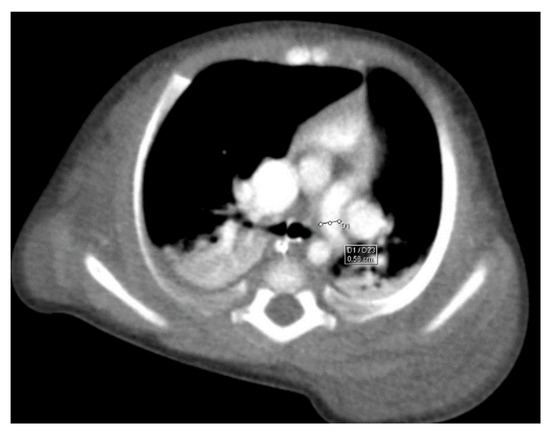

Through thoracic CT, we found SVC with a diameter of 15 mm (Figure 1), a venous collector with a 12 mm in diameter connected to the SVC and identified at the level of a plane passing through the middle of the left superior pulmonary lobe (Figure 2). The venous structure continues superiorly with the left brachiocephalic venous trunk, which was dilated up to 12 mm (Figure 3) and inferiorly with a left pulmonary vein. The pulmonary trunk appeared shorter, with a diameter of 6 mm, right pulmonary artery = 5.4 mm and left pulmonary artery = 5.6 mm (Figure 4 and Figure 5). We have identified traits of pulmonary consolidation (Figure 6).

Figure 1.

Dilated SVC.